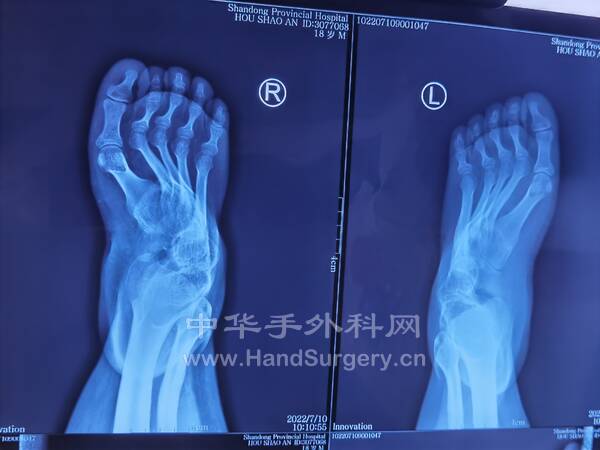

1.男,16岁双足马蹄足,儿麻后遗症,偏瘫,可行手术治疗(图1-5)

IMG_20220717_145337.jpg

IMG_20220717_145256.jpg

IMG_20220717_145332.jpg

IMG_20220717_145420.jpg

IMG_20220717_145413.jpg

IMG_20220717_160542.jpg

马蹄内翻足患者DR片:

双足正侧位(负重位),双踝正侧位(负重位),双下肢全长正位,双跟骨轴位